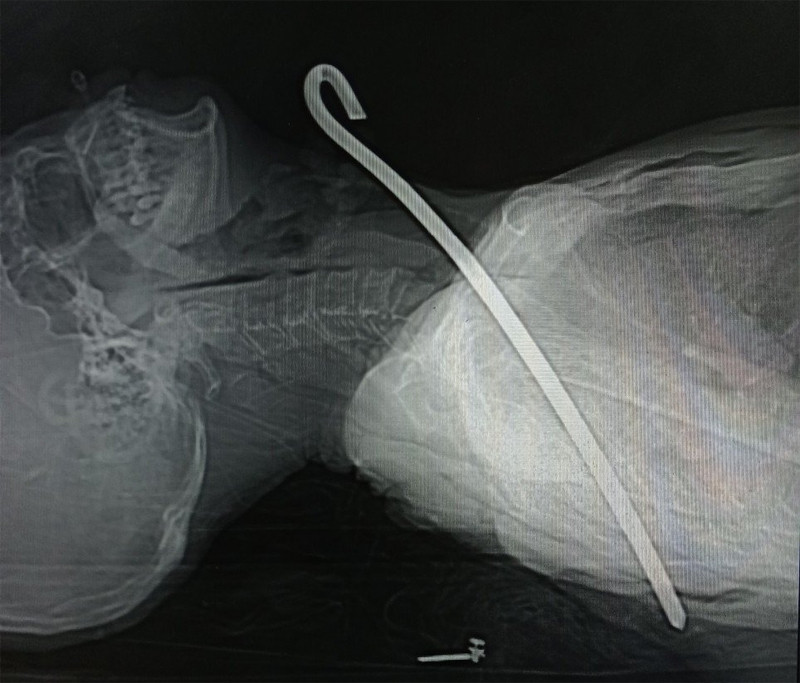

Trước đó, ngày 26/2, ông V.C.Đ. (67 tuổi, trú ở xã Kỳ Tiến, huyện Kỳ Anh) trong lúc dắt bò ngoài đồng về nhà đã không may vấp ngã, bị thanh sắt đâm trúng. Ông Đ. sau đó được đưa vào Bệnh viện Đa khoa Hà Tĩnh nhập viện trong tình trạng bị thanh sắt đường kính 0,8 cm, dài 30 cm đâm xuyên cổ qua phổi phải và trung thất xuống vùng ngực.

Qua thăm khám, bác sĩ chẩn đoán ông Đ. bị tổn thương rách thùy trên phổi phải, tràn khí màng phổi trái, tràn khí dưới da thành ngực và vùng cổ. Ngoài ra bệnh nhân còn bị gãy cung sau xương sườn số 5, 6 bên trái, gãy xương bả vai trái…

| Hình ảnh dị vật đâm xuyên cổ ông Đ. Ảnh: Bệnh viện Đa khoa Hà Tĩnh |

Tiếp nhận bệnh nhân, các bác sĩ đã hội chẩn và chuyển mổ cấp cứu, phẫu thuật mở ngực khâu phục hồi phổi trái, khâu cầm máu động mạch liên sườn, khâu vết thương trung thất trên, lấy dị vật.

Sau hơn 10 ngày nhập viện cấp cứu, sức khỏe bệnh nhân đã ổn định. Dự kiến trong vài ngày tới ông Đ. sẽ xuất viện.